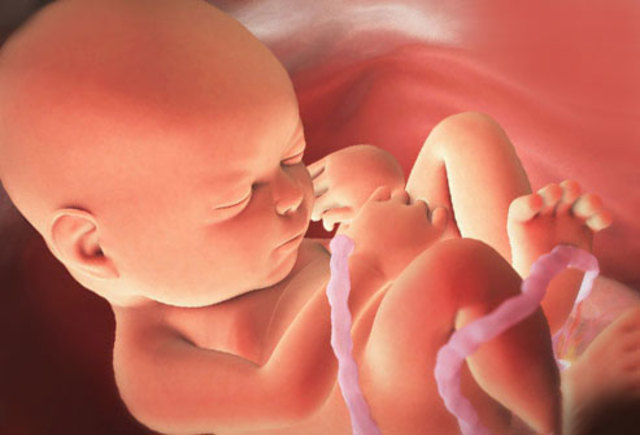

20 weeks is offically half way through the pregnancy. The baby is now about 11 ounces and around 7 inches long. At this point of time the fetus can now recognize their mother's voice and various fetures like their fingernails and hair continue to grow.

• Week Twenty-One Progression